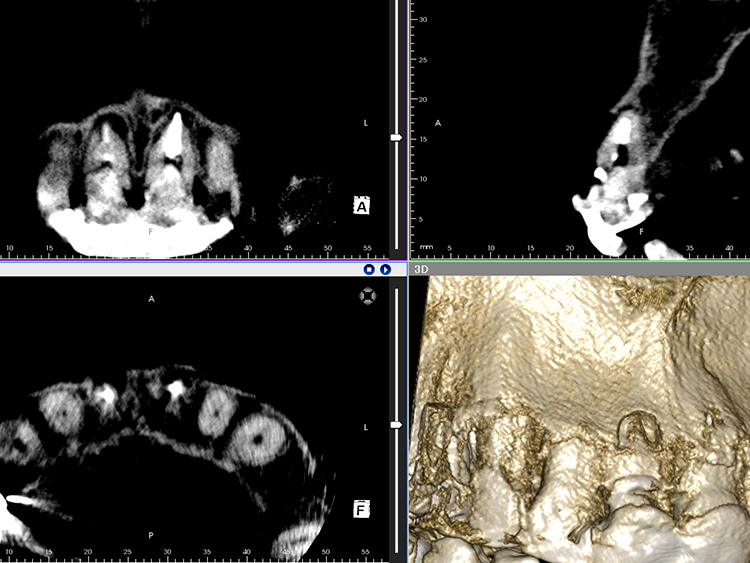

レントゲン検査では、両歯ともに根の先端に大きな病変が認められ、根周囲の骨が広範囲にわたり吸収されていることが確認されました。患者さんご自身の健全な歯質がほとんど残されていない、極めて重症度の高いケースであることがわかります。

レントゲン検査の結果、根の先端にあった病変は治癒し、歯根の周囲に新たな骨の添加が認められます。これは、根管治療で用いた抗菌作用のあるMTAセメントが、カルシウムイオンを持続的に放出することで周囲の硬組織再生を誘導したためと考えられます。